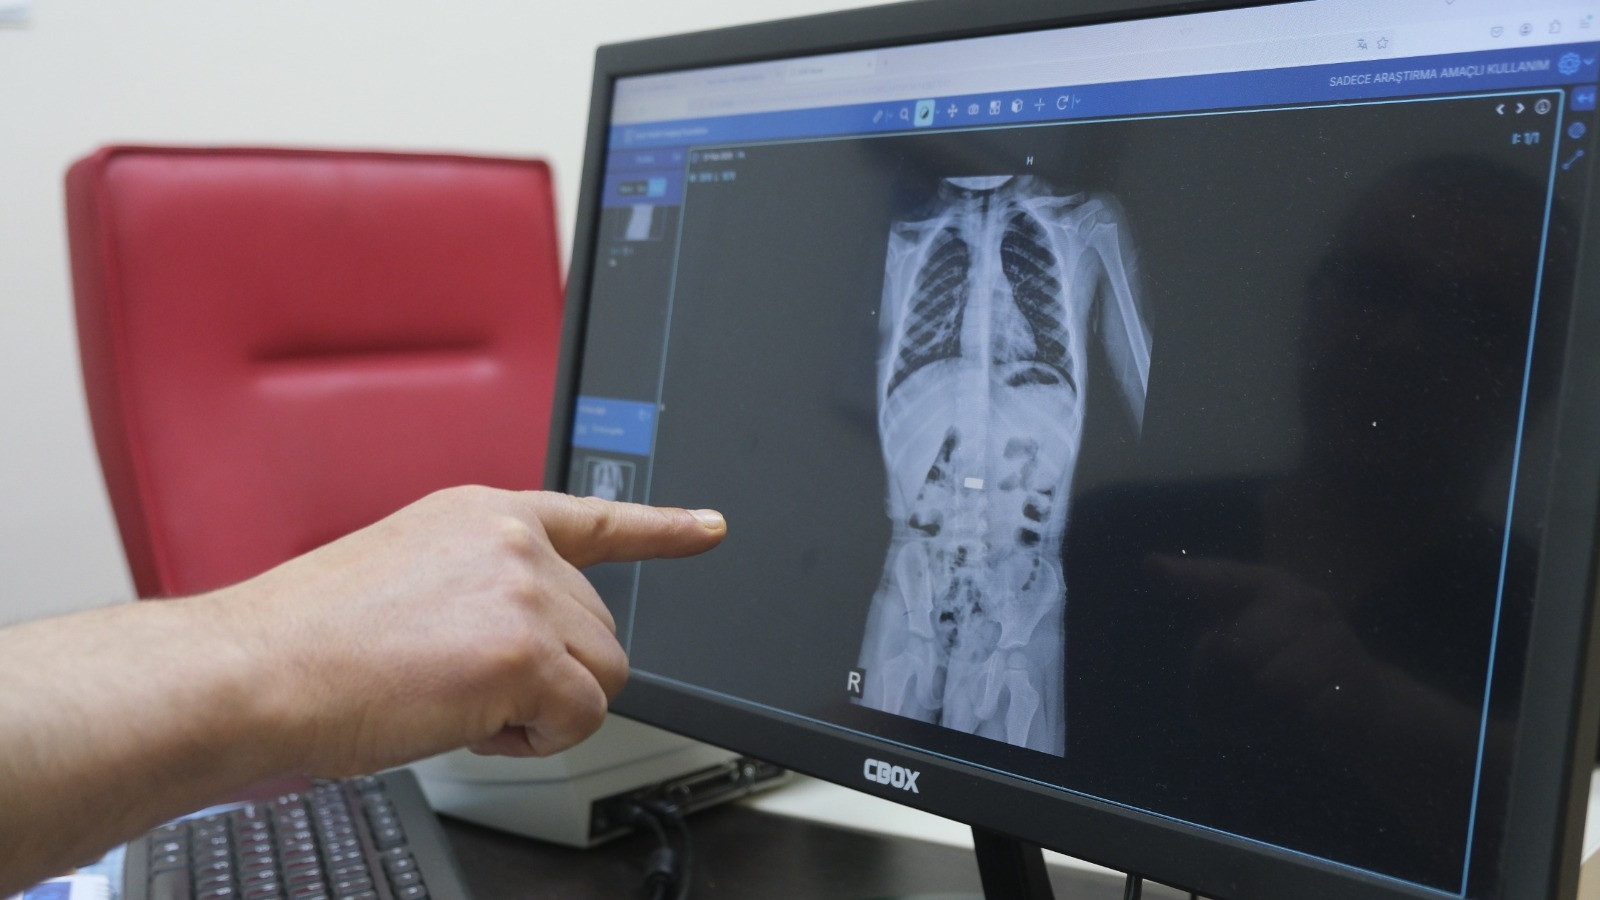

Karaman’da 4 yaşındaki İ.K.’nin mıknatıs yuttuğundan şüphelenen ailesi, Karaman Eğitim ve Araştırma Hastanesi Acil Servisi’ne başvurdu. Yapılan tetkiklerde çocuğun ince bağırsağında iki adet mıknatıs bulunduğu tespit edildi. Gözetim altına alınan çocuğun sağlık durumu 5 gün boyunca takip edildi. Çocuk Cerrahisi Uzmanı Doç. Dr. Mehmet Uysal’ın gerçekleştirdiği operasyonla bağırsakta tıkanıklığa yol açan iki mıknatıs başarılı bir şekilde çıkarıldı.

Hastayı 5 gün boyunca takibe aldıklarını belirten Doç. Dr. Mehmet Uysal, gözetim süresince çekilen filmlerde mıknatısların yer değiştirmediğini söyledi.

Uysal, “Hastayı genel anestezi altında ameliyata aldık. İnce bağırsakta iki mıknatısın birbirine yapışık halde olduğunu gördük. Gerçekleştirdiğimiz operasyonla mıknatısları çıkardık. Ameliyat sonrası hastamız üçüncü gününde taburcu edildi. Şu an genel durumu iyi” dedi.